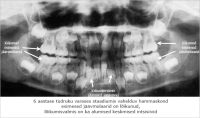

Kaaries

4